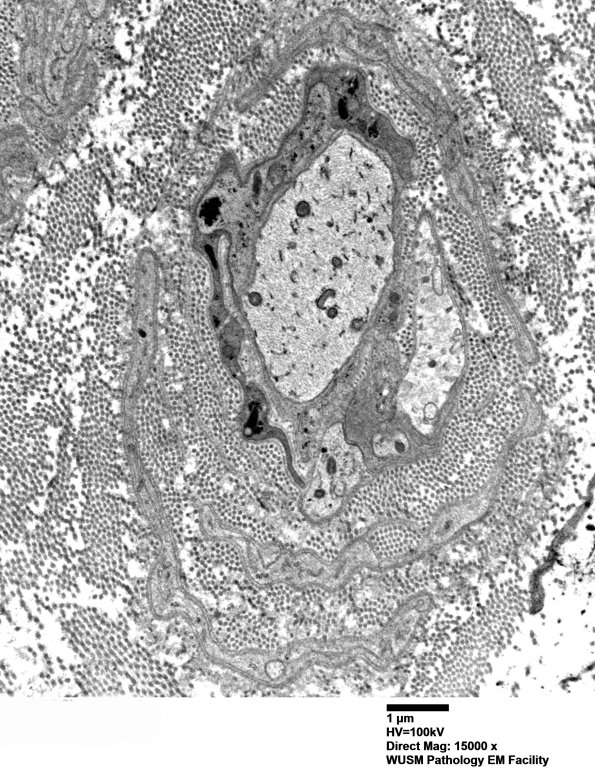

5B7,8 Although typical onion-bulbs with thin Schwann cell concentric processes separated by collagen were not present, there are collections of thicker Schwann cell processes, some containing axons, arranged concentrically around demyelinated axons. A few of these may represent pseudo-onion bulbs but many are very suggestive of true onion bulbs. The absence of remyelination in this nerve biopsy is quite striking and unusual. (electron micrographs)